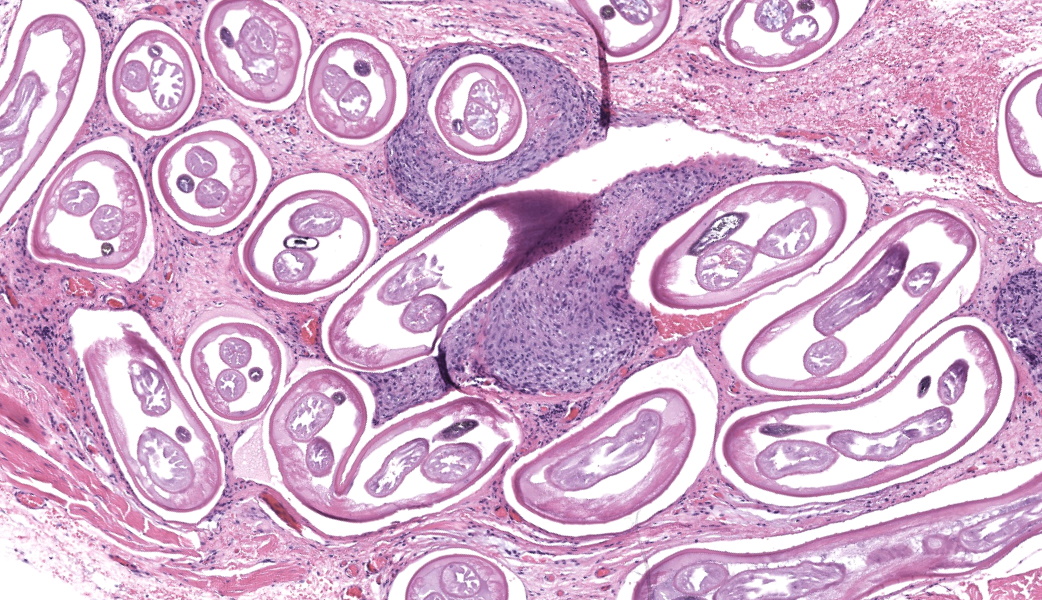

Enucleated right eye: Expanding and infiltrating the sclera, and occasionally extending to and dissecting the periocular skeletal muscle, are multiple cross and oblique sections of nematode parasites. Nematodes are characterized by a thick cuticle with annular ridges seen as raised areas in oblique sections, coelomyarian/polymyarian musculature that is atrophied and multifocally replaced by hypodermal tissue, a very small intestinal cross section, and reproductive organs. Mild hemorrhage, fibrin, and edema are present in affected sclera, and occasional nematode cross sections are surrounded by epithelioid macrophages. The cornea is hypercellular with low numbers of neutrophils and areas of neovascularization.Contributor's Morphologic Diagnoses:

Onchocerca lupi is typically diagnosed via histopathology, and to our knowledge no commercially available polymerase chain reaction (PCR) tests is available, although PCR assays have been described in the peer reviewed literature.7,14 Typical histologic lesions include nematodes with very small intestinal cross sections, atrophied coelomyarian/polymyarian musculature, and annular cuticular ridges that can be seen in longitudinal or oblique sections. Microfilaria may be seen within female worms. Variable amounts of inflammation ranging from mild to severe, and including macrophages, lymphocytes, and eosinophils may be seen, as can fibroplasia. We have seen pyogranulomatous inflammation as well in our laboratory. Currently, a commercially available serology test is not available, although serologic tests are in development.15

This third case stimulated excellent discourse on ocular pathology and the associated changes seen in this eye. While the nematodes in the periocular tissues were striking, the other ocular lesions were a point of discussion focus for conference participants to ensure residents in attendance understood the importance of not getting “pigeon-holed” onto one lesion before examining the tissues in their entirety. This eye had multiple other lesions, some of which were subtle, and these caught the attention of the more experienced participants in the room. The keratitis in this eye served as a springboard to discuss the other changes, and conference participants suspect the keratitis was secondary to melanosis and inflammation causing occlusion of the drainage angle in this case, resulting in secondary glaucoma (as evidenced by degeneration of inner retinal cells and retinal ganglion cell loss) and subsequent buphthalmia. One of the more common sequelae to buphthalmia is an exposure keratitis due to inability of the eyelids to completely close over the enlarged eye. Coupled with possible irritation from the nematodes, participants felt that the keratitis and precluding factors were important features to discuss in this case.Conference participants unanimously agreed that the nematodes in section were consistent with Onchocerca lupi. For the sake of educational discussion, differentials for ocular nematodes in a dog were: Toxacara canis (ascarid), Onchocerca lupi (spirurid), Angiostrongylus vasorum (metastrongylid), Dirofilaria immitis (spirurid), Ancylostoma caninum (strongylid), Trichinella spiralis (aphasmid), and Thelazia spp. (spirurids). Of these, Thelazia spp. are the true ocular parasite and tend to reside in the conjunctival sacs and lacrimal ducts of infected animals. Onchocerca spp. in other species were briefly discussed, and honorable mentions included O. cervicalis, which sets up shop in the nuchal ligament of horses, O. gutturosa and O. lienalis, both of which invade the nuchal and gastrosplenic ligaments of cattle, and O. volvulus, the causative agent of “river blindness” in humans.